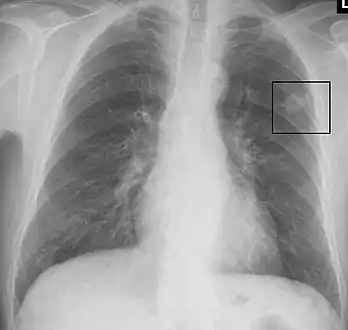

Lung adenocarcinoma with Lambert Eaton myasthenic syndrome-lesion shows proliferation of infiltrating atypical epithelial cells with cribriform or papillary structures Chest X-ray showing a tumor in the left lung (right side of the image)

Chest X-ray showing a tumor in the left lung (right side of the image)

Blood tests may be performed to exclude other causes of muscle disease (elevated creatine kinase may indicate a myositis, and abnormal thyroid function tests may indicate thyrotoxic myopathy). Antibodies against voltage-gated calcium channels can be identified in 85% of people with EMG-confirmed LEMS.[4] Once LEMS is diagnosed, investigations such as a CT scan of the chest are usually performed to identify any possible underlying lung tumors. Around 50–60% of these are discovered immediately after the diagnosis of LEMS. The remainder is diagnosed later, but usually within two years and typically within four years.[5] As a result, scans are typically repeated every six months for the first two years after diagnosis.[4] While CT of the lungs is usually adequate, a positron emission tomography scan of the body may also be performed to search for an occult tumour, particularly of the lung.[9]